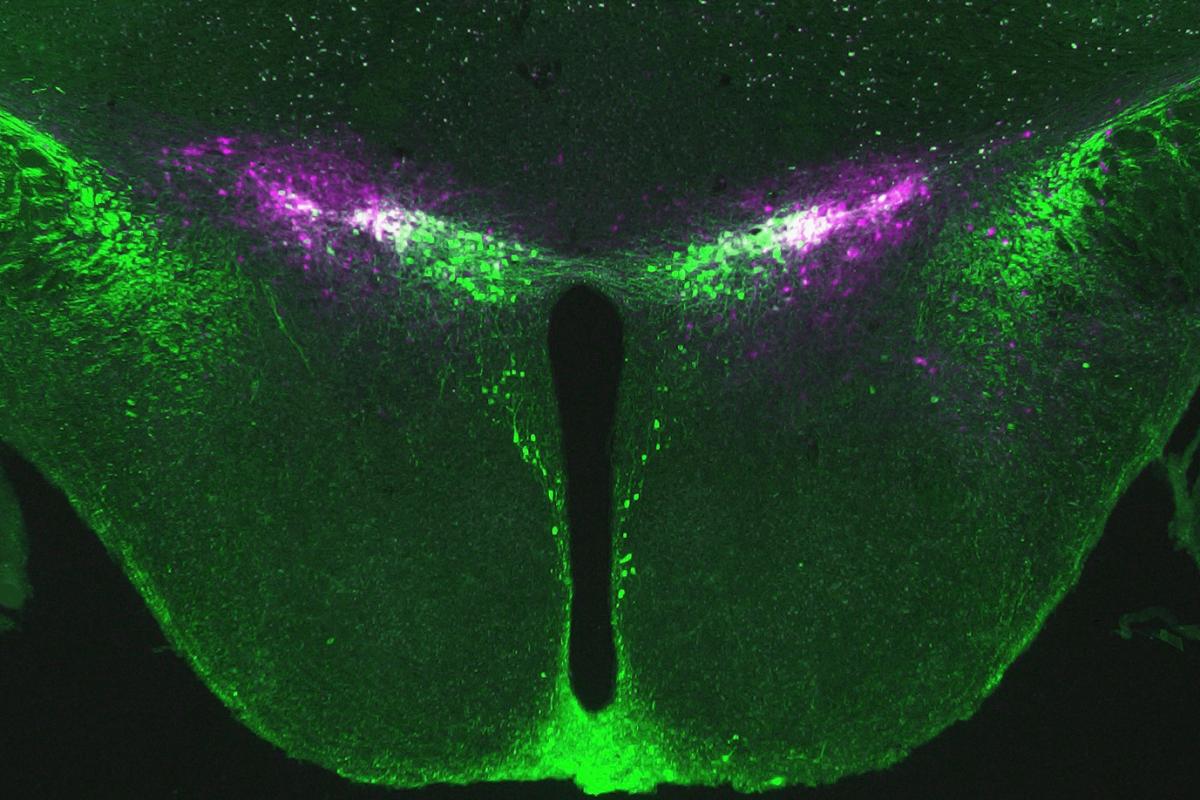

Dopamine neurons in the zona incerta. (Photo Courtesy of Zhang Laboratory)

Working in mouse models, Zhang, along with doctoral student Qiying Ye and research assistant Jeremiah Nunez, isolated a tiny group of dopamine neurons within the zona incerta that activate quickly to drive food-seeking behavior when the body’s energy levels dip and deactivate while food is consumed. Dopamine, known as the “feel-good” neurotransmitter, acts in the brain’s reward system, and current research suggests a group of specific dopamine neurons drives homeostatic food seeking.

Human behaviors, including the desire to eat, are the result of complex processes in our brains, and scientists are still learning about the mechanisms that control these functions. Zhang’s research team has found the zona incerta, a region deep in the brain’s core that is not well understood, plays a critical role in controlling eating behaviors.